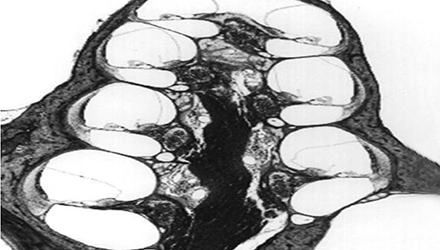

梅尼埃病是以膜迷路積水為基本病理改變,以發(fā)作性眩暈、聽力下降、耳鳴和耳脹滿感為臨床特征的特發(fā)性內(nèi)耳疾病。

單側(cè)發(fā)病患者約占85%,累及雙側(cè)者常在3年內(nèi)先后發(fā)病,發(fā)病年齡大多在30~50歲,無明顯性別特征。